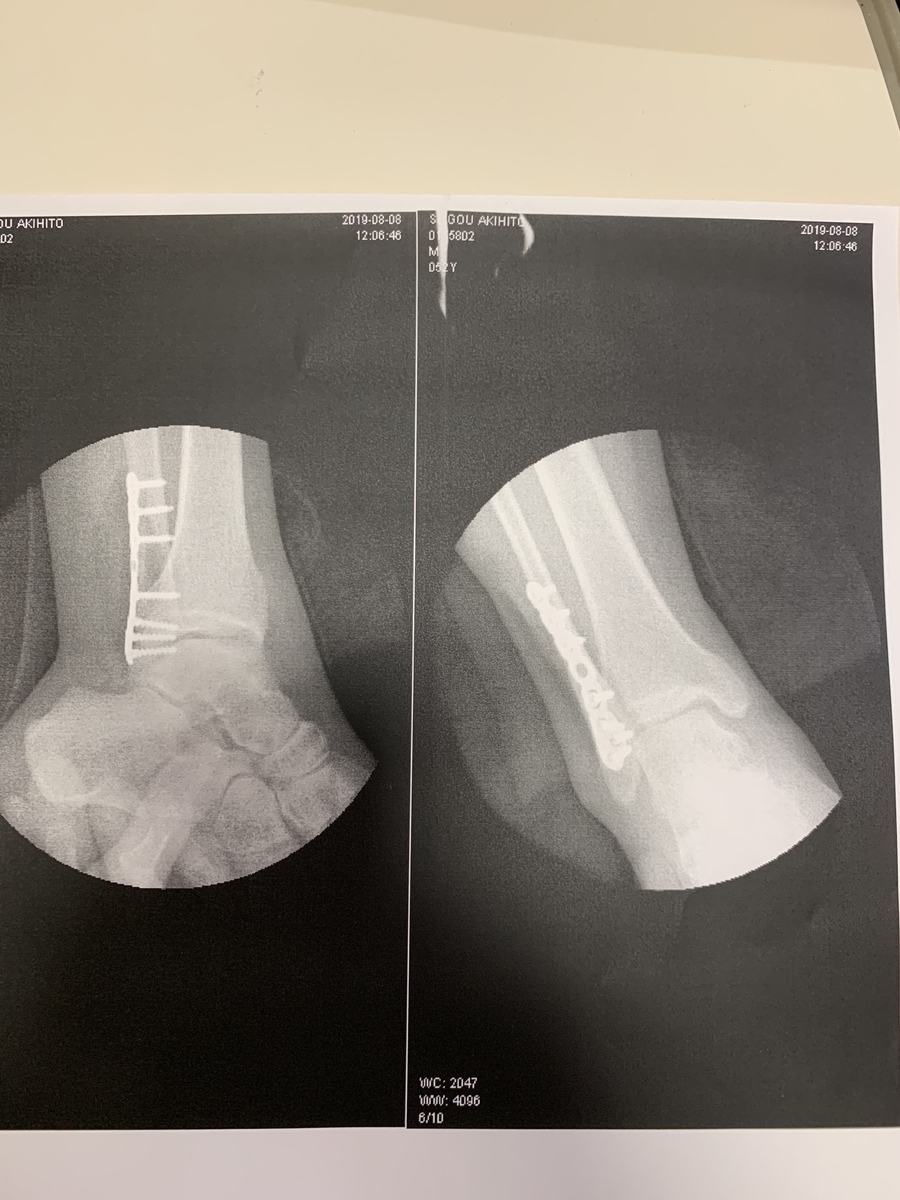

右上腕粉砕骨折

右足外果骨折

お医者さんに強化パーツ組み込んでもらいました、グロ画像にならんよう小さく貼ります

そのほか足の平の部分バイクにすりつぶされるように捻ったので筋は全部負傷し爪もつぶされて内出血で紫になってます